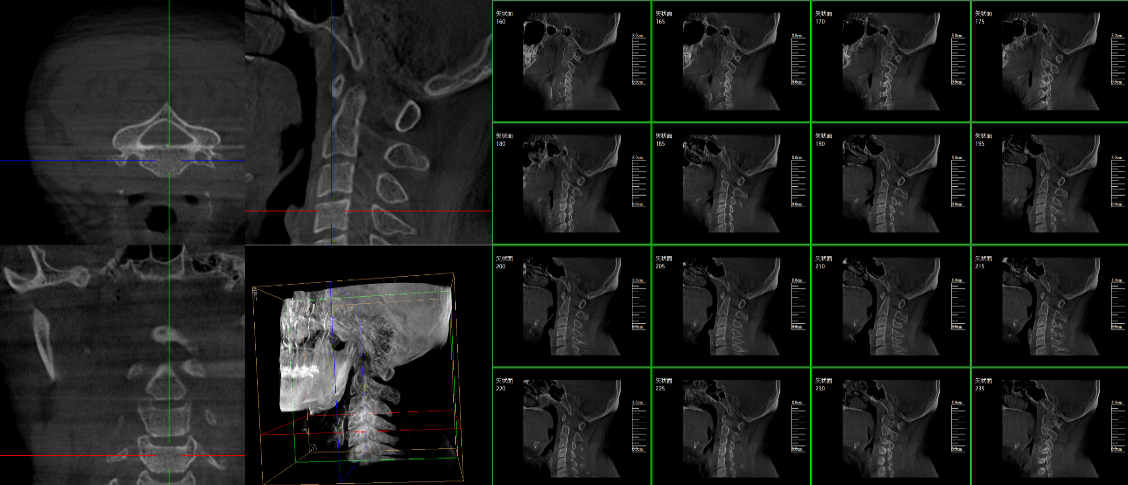

現(xiàn)在很多廠家或者經(jīng)銷商都在推廣三維c型臂,那么,三維c型臂是什么意思?三維c型臂是一款新型C形臂,實(shí)現(xiàn)了術(shù)中影像從二維到三維的飛躍。通過不同方位的斷層圖像,能夠更清晰、完整地顯示椎體及其附件的解剖學(xué)結(jié)果,直觀地分析病變與周圍組織的立體空間關(guān)系,三維斷層成像能夠使手術(shù)模擬和手術(shù)方案的制定更加準(zhǔn)確。

脊柱外科的應(yīng)用:有研究表明,在三維c型臂圖像引導(dǎo)的下頸椎或胸椎后路螺釘置入術(shù)中,螺釘正確置入率可達(dá)92.7%,在三維c型臂圖像引導(dǎo)的椎間孔腰椎椎間盤融合術(shù)中,術(shù)者被輻射總量明顯降低。此外三維c型臂可以搭配骨科手術(shù)導(dǎo)航和機(jī)器人使用,能將該過程智能化和準(zhǔn)確化,進(jìn)一步提高螺釘?shù)闹踩肼省?/span>

創(chuàng)傷外科的應(yīng)用:由于創(chuàng)傷外科的患者多數(shù)為急、重癥患者,以致術(shù)前準(zhǔn)備時(shí)間較短,很多都需行急診手術(shù),三維c型臂可以在術(shù)中實(shí)時(shí)重建三維圖像,使手術(shù)醫(yī)生對(duì)一些復(fù)雜骨折更加充分的了解,并且能夠在術(shù)中即時(shí)校正螺釘?shù)奈恢?,更加精確地置入固定器材,減少術(shù)中及術(shù)后發(fā)生并發(fā)癥的幾率,極大限度地縮短螺釘置入時(shí)間。